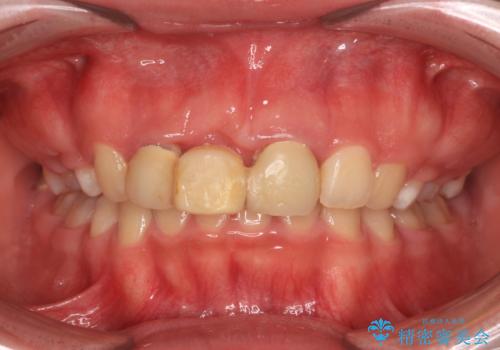

- 矯正治療中に装着していた仮歯を綺麗にしたいとのことで来院された患者様です。

小学生の頃に歯をぶつけて抜歯となりブリッジを装着したそうですが、その後矯正治療を行うに当たりブリッジを切断したとのことでした。

残っている歯根の状態はあまり良くなく、長期的な予後を考えると抜歯を検討するべきでしたが、20代前半という年齢を考え、オールセラミックブリッジにて補綴治療を行うこととしました。